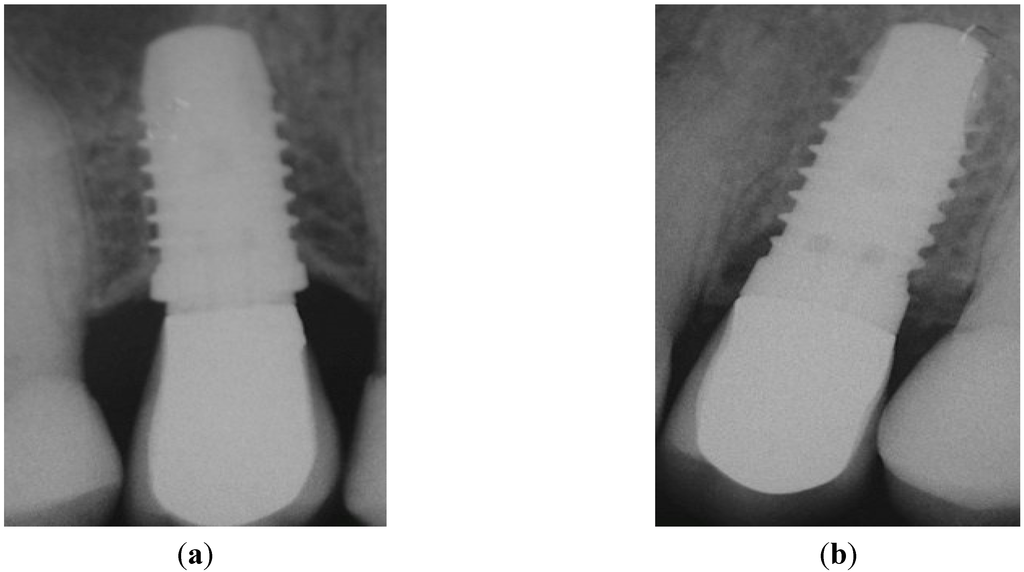

Figure 5.

Peri-apical X-rays taken after AC. (a) Position 15; (b) Position 25. No pathological signs were visible around both implants.